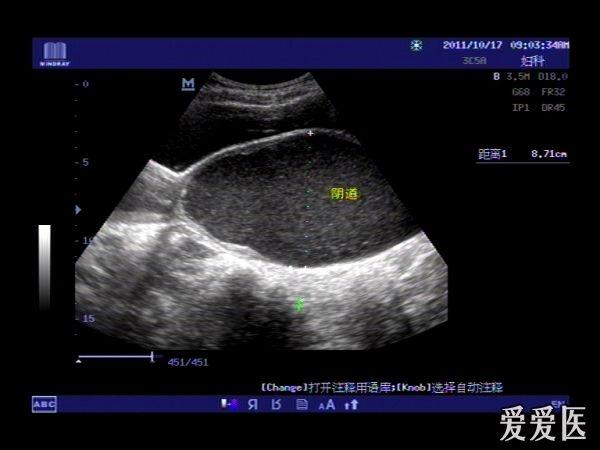

患者,女,14岁,因周期性下腹部胀痛不适3月余来我院就诊。查体:下腹部可扪及一包块。超声检查膀胱适度充盈,子宫前倾位,宫底部上移至脐平面,宫体宫腔,宫颈及**明显扩张呈椭圆形,内回声不纯净,呈细密的点状回声,宫内膜显示清晰。超声诊断处女膜闭锁